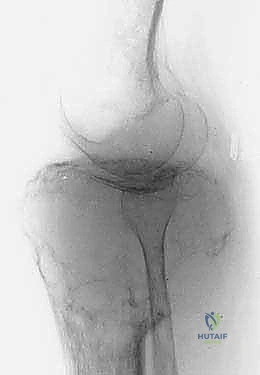

لفهم مدى تعقيد وعبقرية جراحة استئصال الظنبوب القريب، من الضروري الإبحار في أعماق التشريح الأساسي لهذه المنطقة الحيوية. لا يقتصر الأمر على مجرد عظام، بل هو نظام هندسي وبيولوجي متكامل ومعقد. يتكون مفصل الركبة من التقاء عظم الفخذ (Femur) من الأعلى، وعظم الساق أو الظنبوب (Tibia) من الأسفل، وعظم الشظية (Fibula) الجانبي، بالإضافة إلى الرضفة أو صابونة الركبة (Patella) في الأمام. الجزء القريب من الظنبوب هو الجزء العلوي العريض من عظم الساق، والذي يشكل القاعدة الأساسية التي يستند عليها مفصل الركبة ويتحمل وزن الجسم بأكمله.

تُعد الأورام الخبيثة التي تنشأ من العظم نفسه هي السبب الأكثر شيوعاً لإجراء هذه الجراحة. منطقة الركبة (أسفل الفخذ وأعلى الساق) هي الموقع المفضل لنمو هذه الأورام، خاصة لدى الأطفال والمراهقين والشباب. تشمل هذه الأورام:

* الساركوما العظمية (Osteosarcoma): وهو النوع الأكثر شيوعاً، ينشأ في الخلايا المكونة للعظم، ويتميز بنموه السريع والعدواني وتدميره للعظم المحيط.